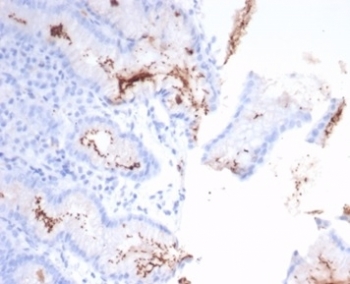

IHC staining of H. pylori-infected FFPE human stomach tissue with Helicobacter pylori antibody (clone HPYL/7226). HIER: boil tissue sections in pH 9 10mM Tris with 1mM EDTA for 20 min and allow to cool before testing.

IHC staining of FFPE H. pylori-infected human stomach tissue with Helicobacter pylori antibody (clone HPYL/7226). HIER: boil tissue sections in pH 9 10mM Tris with 1mM EDTA for 20 min and allow to cool before testing.

The spiral shaped bacterium Helicobacter pylori is strongly associated with inflammation of the stomach and is also implicated in the development of gastric malignancy. H. pylori is known to cause peptic ulcers and chronic gastritis in human. It is associated with duodenal ulcers and may be involved in development of adenocarcinoma and low-grade lymphoma of mucosa associated lymphoid tissue in the stomach. This antibody stains the individual H. pylori bacterium when it presents on the surface of the epithelium or in the cytoplasm of the epithelial cells in biopsy tissue sections from the antrum and body of the stomach.